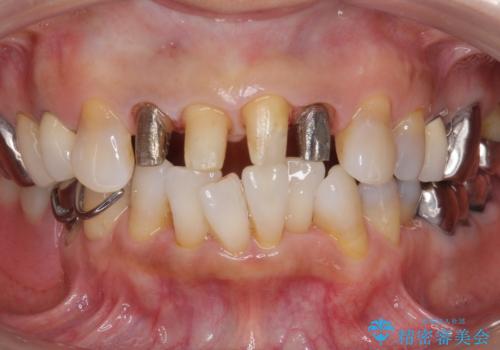

- 前歯の詰め物が頻繁に外れるとのことで来院。

これを機にセラミックでかぶせて、前歯の歯並びも良くしたいとのことでした。

左上の前歯のみねじれが大きいため、歯の位置をひっこめたかぶせものにするために、神経の治療を行っています。

- 59.5万円 (オフィスホワイトニング 3万円、ジルコニアクラウン スタンダード 10万円×4本、仮歯 1万円×4本、精密根管治療(左上1)6万円×1本、ファイバーコア 2万円×1本)費用は治療当時の料金となります

両側の前歯もやり替えをすることで、前歯の前突感も無くしています。

両側の歯の神経の治療および土台のやり替えは行っていません。